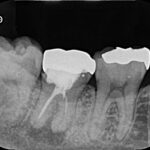

すでに前医にて、根管治療が行われていた状態でした。治療開始前の状態が不目なため正確な判断はできませんが、ラバーダムの使用はされておらず、歯茎の腫れ(フィステル)が残存し疼痛もあるため、再根管治療を行いました。

下顎前歯は歯自体が細いため、歯にストレスを加えないよう最大限留意しながら(クラックを防ぐため)、治療を進めました。

| 根管充填 | バイオセラミックシーラーを用いたHydraulic condensation technique |

術後、3、6、12ヶ月の経過観察を行いました。6ヶ月時点では根尖部の透過像は残っていましたが、12ヶ月時点で根尖部の骨吸収像は消失し、良好な経過をたどっています。